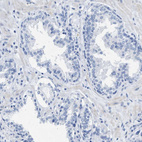

Immunohistochemistry analysis in human heart muscle and prostate tissues using HPA018174 antibody. Corresponding HHATL RNA-seq data are presented for the same tissues.